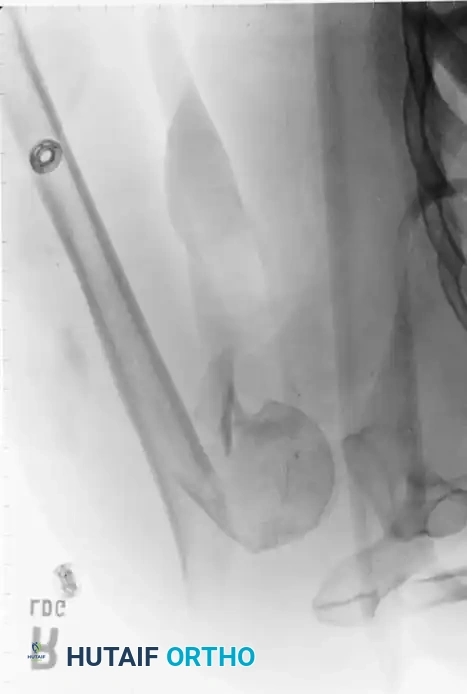

Percutaneous Pinning

Percutaneous pinning offers the distinct advantage of avoiding extensive soft-tissue dissection, thereby maximally preserving the blood supply to the humeral head. It is a minimally invasive, cost-effective technique. Jaberg et al. and Resch et al. have reported excellent outcomes using threaded pins or Kirschner wires.

Technique Overview:

* Closed reduction is achieved under fluoroscopy using traction, abduction, and manipulation.

* Pins are introduced percutaneously from the lateral humeral cortex, directed superomedially into the humeral head.

* Additional pins may be placed anteriorly to secure the lesser tuberosity or superiorly for the greater tuberosity.

* Warning: The axillary nerve is at risk during lateral pin insertion. Pins must be placed carefully, often utilizing a small stab incision and blunt dissection to the bone.